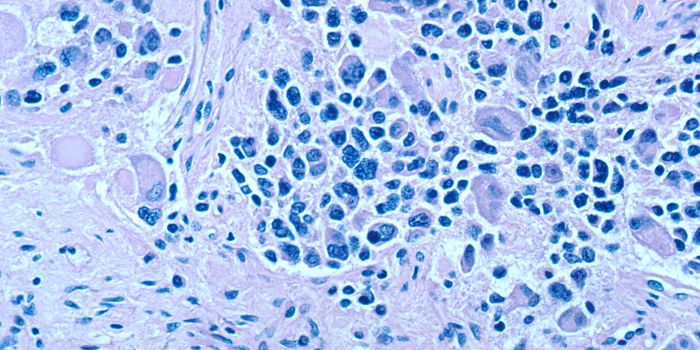

OCT 07, 2021CancerNeuroblastoma is a cancer of immature nerve cells found in various areas, including the adrenal glands, neck, chest ...